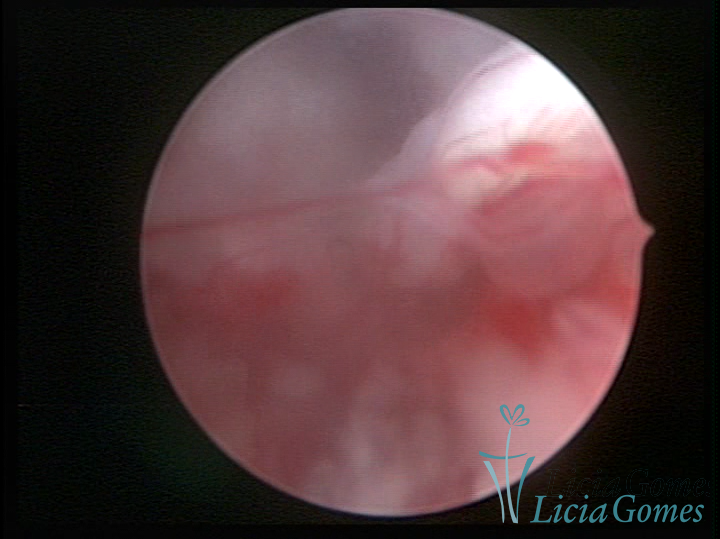

Este pode apresentar uma gama variável de aspectos macroscópicos, com aspecto pseudopolipoide; lembrando tecido cerebroide ou com reação deciduoide;a vascularização superficial é mais evidente e com vasos em formatos de saca-rolha ou espirais visualizando também a vascularização com atípias, com aumento do calibre dos vasos superficiais, pode ser encontrado também tecido em necrose, poderá haver um pequenos dendritos (papilomatoso).